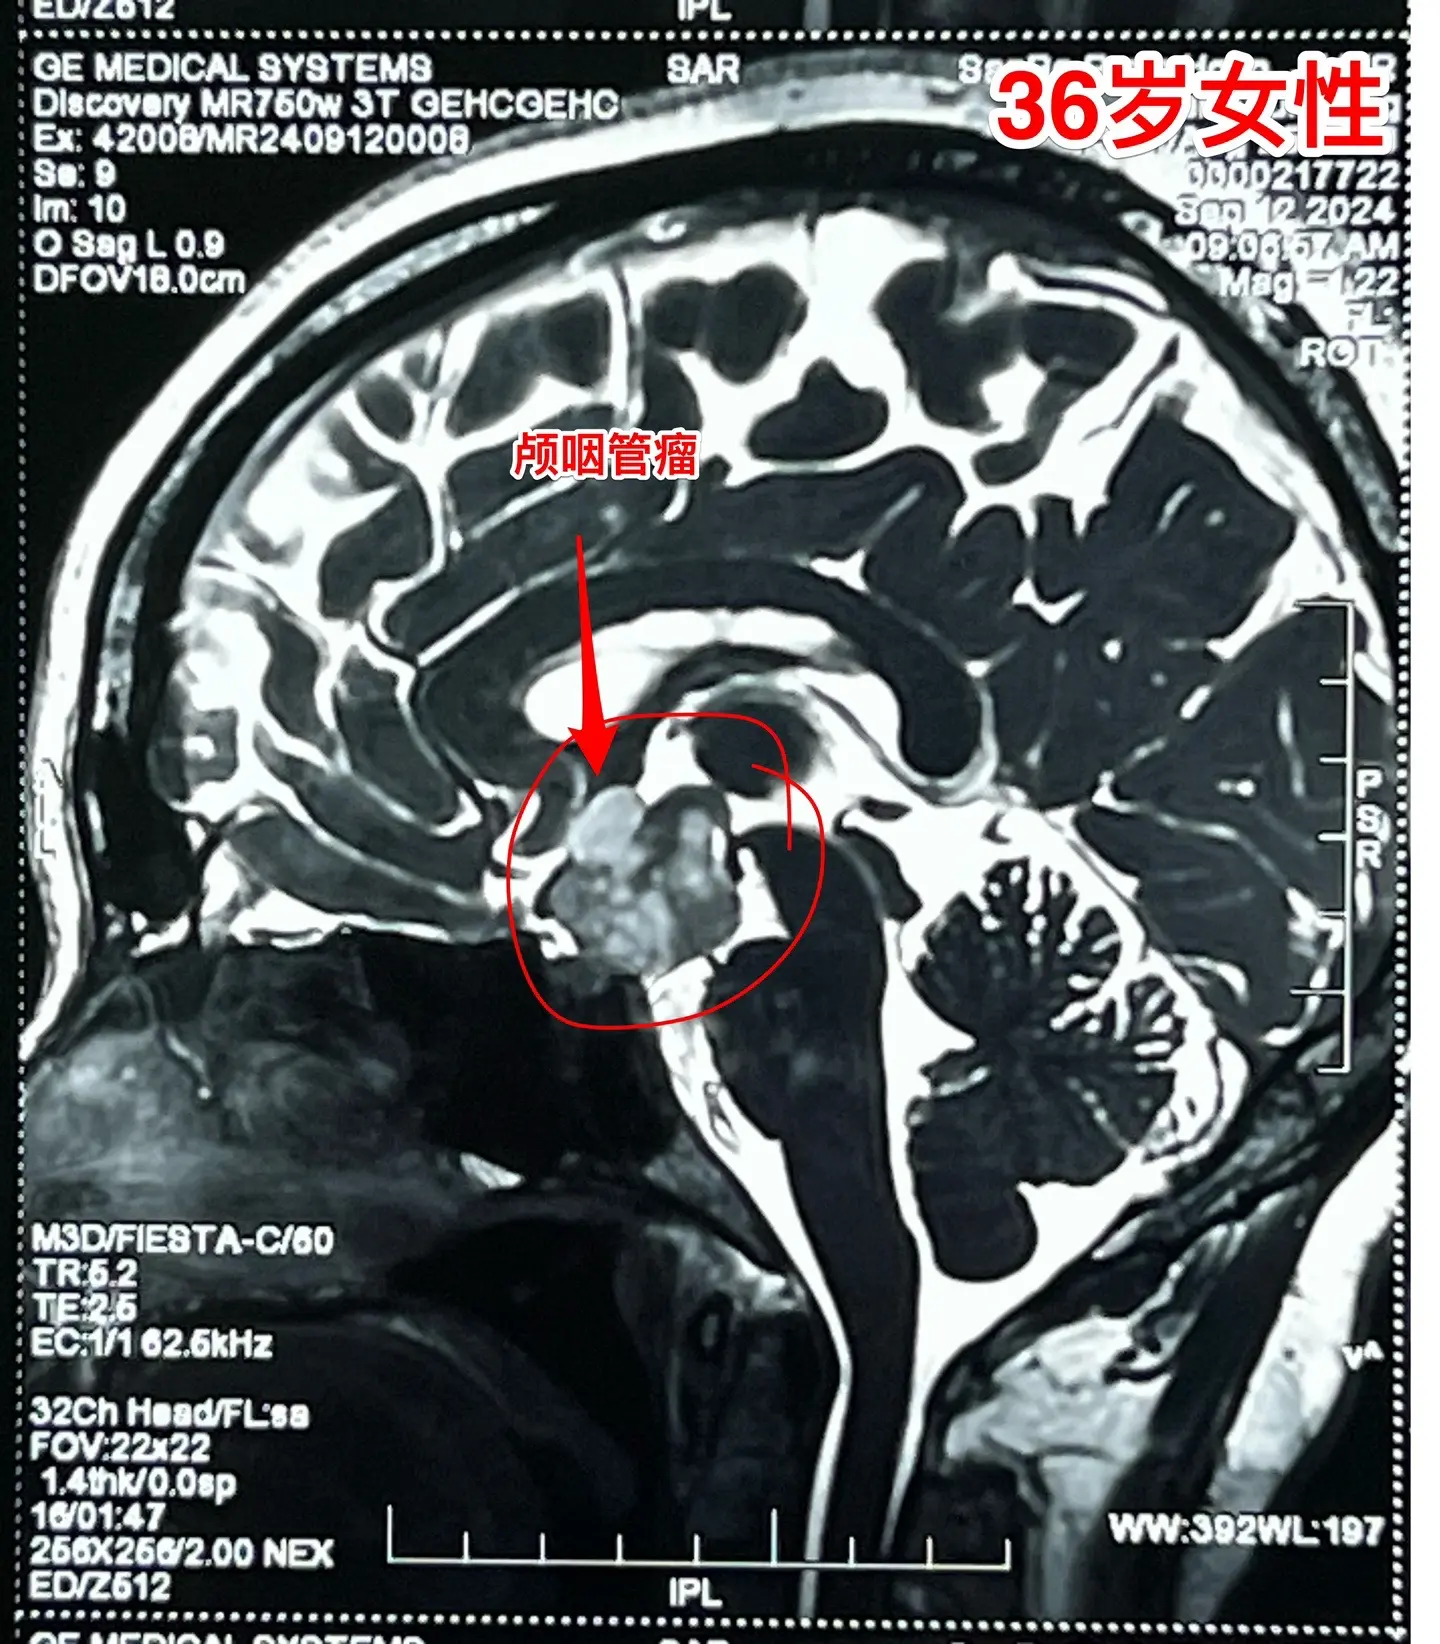

36岁玉溪市女性,颅咽管瘤手术后视力改善。一开始出现内分泌紊乱,随后出现头痛、视力下降。发现颅咽管瘤后于9月11日到我科住院,因为发烧,等到9月24日才作了手术。 好饭不怕晚!手术很顺利,肿瘤得到完全切除,垂体柄保留了30%。手术后病人的身体恢复很快,视力也好转了。